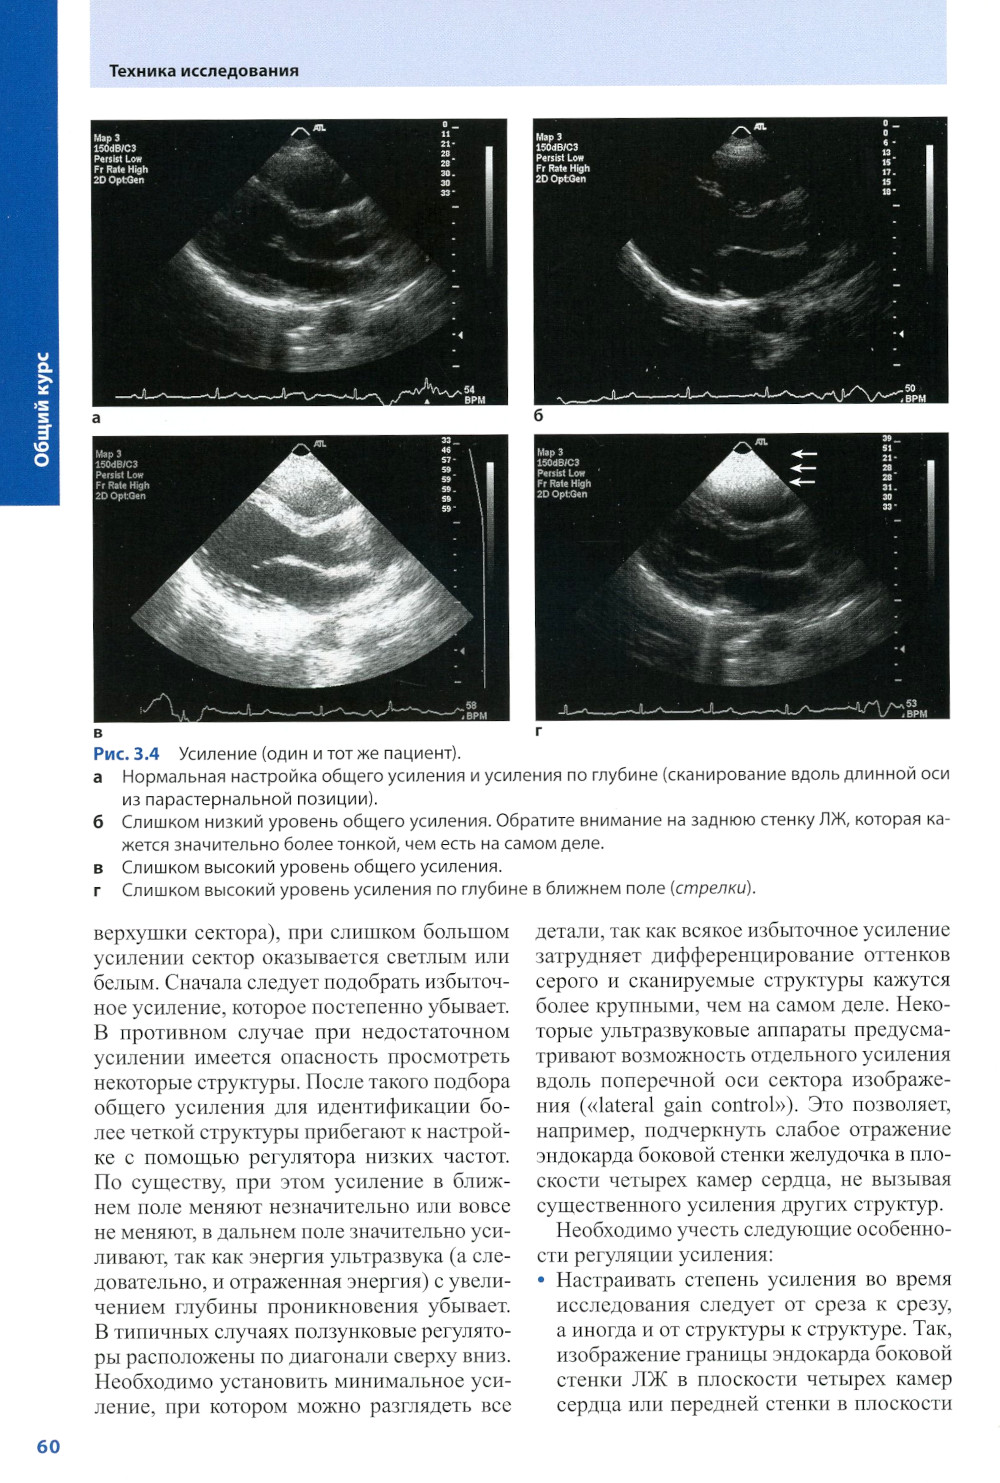

В книге рассмотрены физико-технические основы ЭхоКГ без излишней детализации, которая может затруднить усвоение клинического материала, методика проведения трансторакальной и чреспищеводной ЭхоКГ и ее основные режимы: М-режим, двух- и трехмерная ЭхоКГ, допплеровское исследование со всеми его вариантами, в частности непрерывно-волновой допплерографией, импульсно-волновой, тканевой допплерографией, цветовым и энергетическим допплеровским картированием. Разбираются клинические ситуации, часто допускаемые ошибки и причины неправильной интерпретации результатов. Описана эхокардиографическая диагностика типичных неотложных состояний, наблюдающихся в практике кардиолога и интерниста.